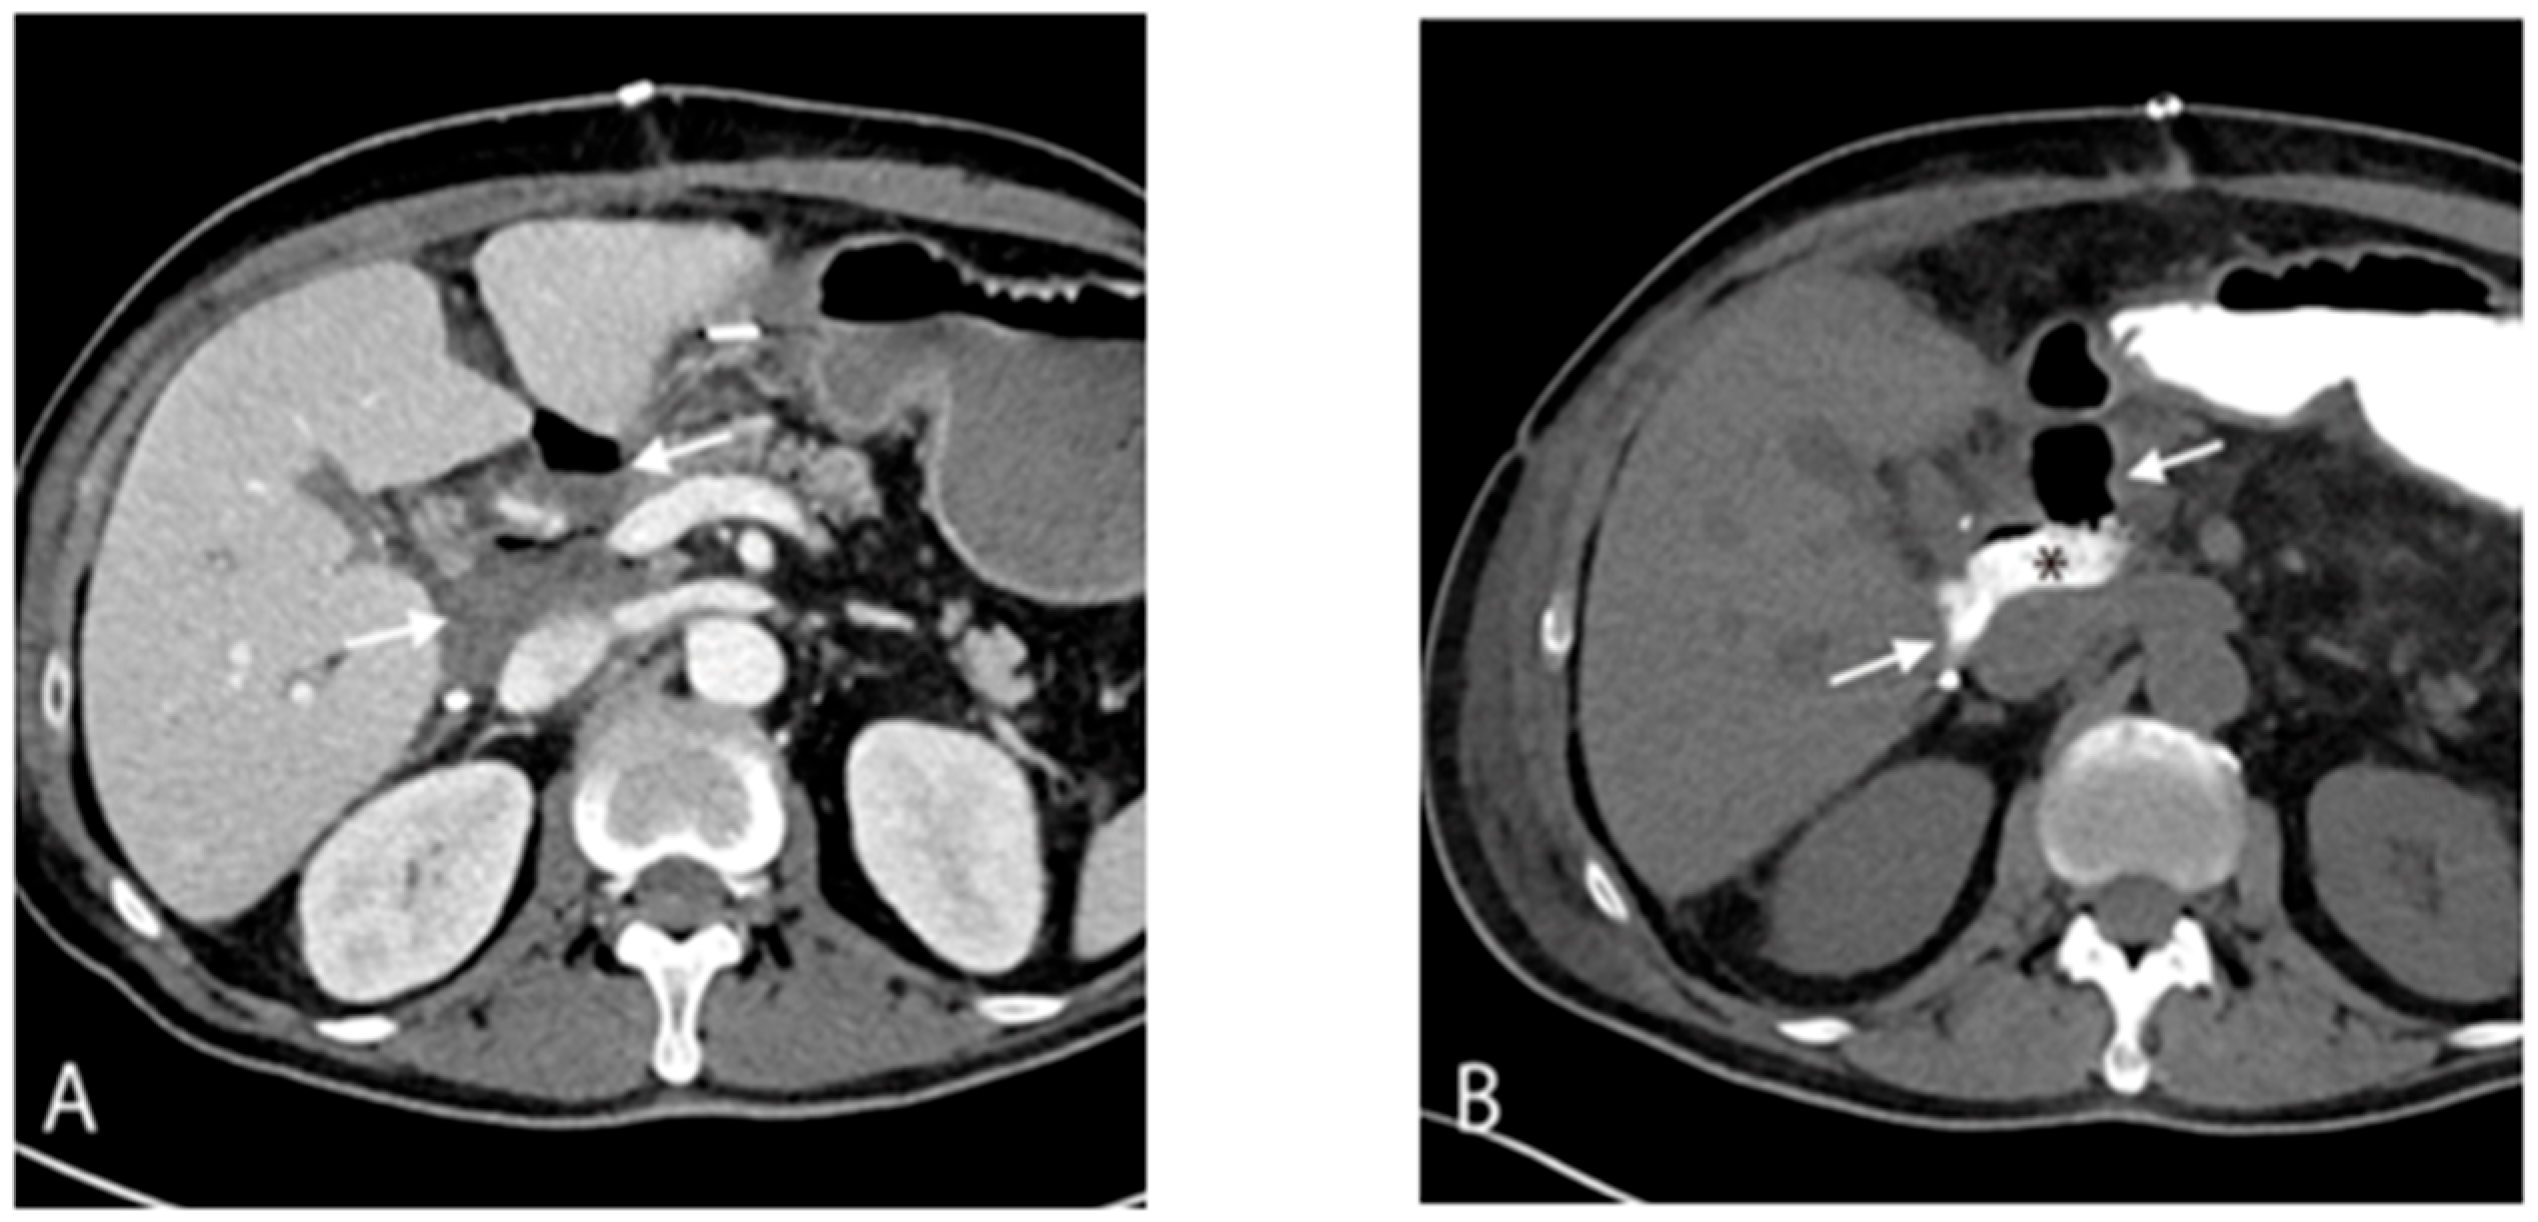

| Mid-August (Day 33) | CT: septic thrombophlebitis/enterocaval fistula from duodenal perforation → endoscopic closure with surgical clip | Bloodstream isolates showed daptomycin resistance on susceptibility testing. |